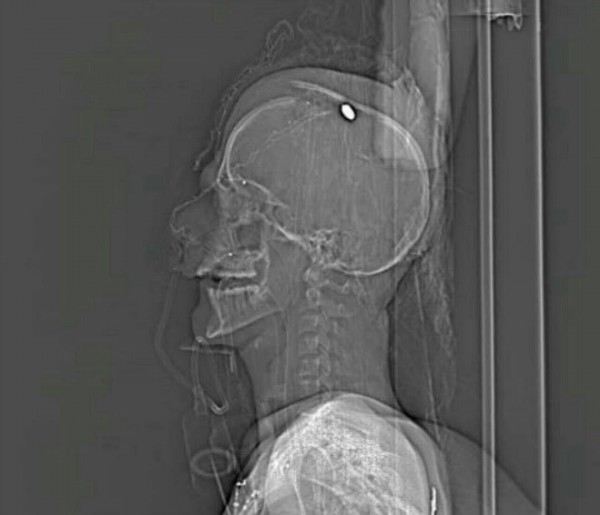

Mostafa now stands between life and death with a swollen eye, many cuts and bruises on his face and a bullet sunken in his head. This innocent 17-year-old youth's life is at stake now as a result of the regime's ongoing crackdown on the people's freedoms and rights.

Months of nonstop camping in the open protest site outside the house of Bahraini Shia spiritual leader Ayatollah Sheikh Isa Qassim ended with a bullet in Mostafa's head. Months of ongoing protests and long bitter nights at the camping site in Diraz ended with a bullet in Mostafa's head, a bullet that the doctors have failed to remove- a bullet fired by cowardly masked forces that attacked the Diraz square and fled. It's a bullet fired by a force affiliated to a spineless authority that still hasn't dared to reveal itself publicly. Why? That is because it no longer has any need to lie.